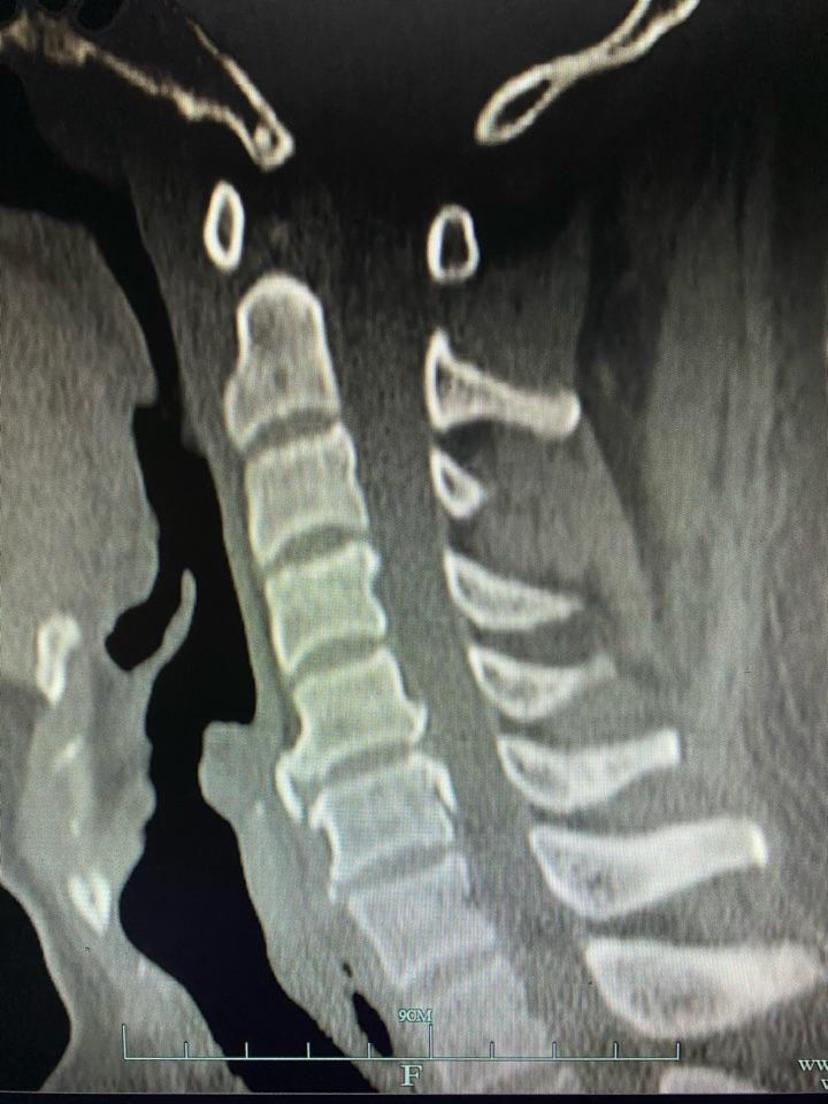

CT显示颈5-6层面后纵韧带骨化及大量骨赘

脱出的椎间盘及骨化物全部去除,术中出血共30ml

采用颈前路微创手术致压物完全去除,位置良好,术后不适症状完全消失,三天康复出院